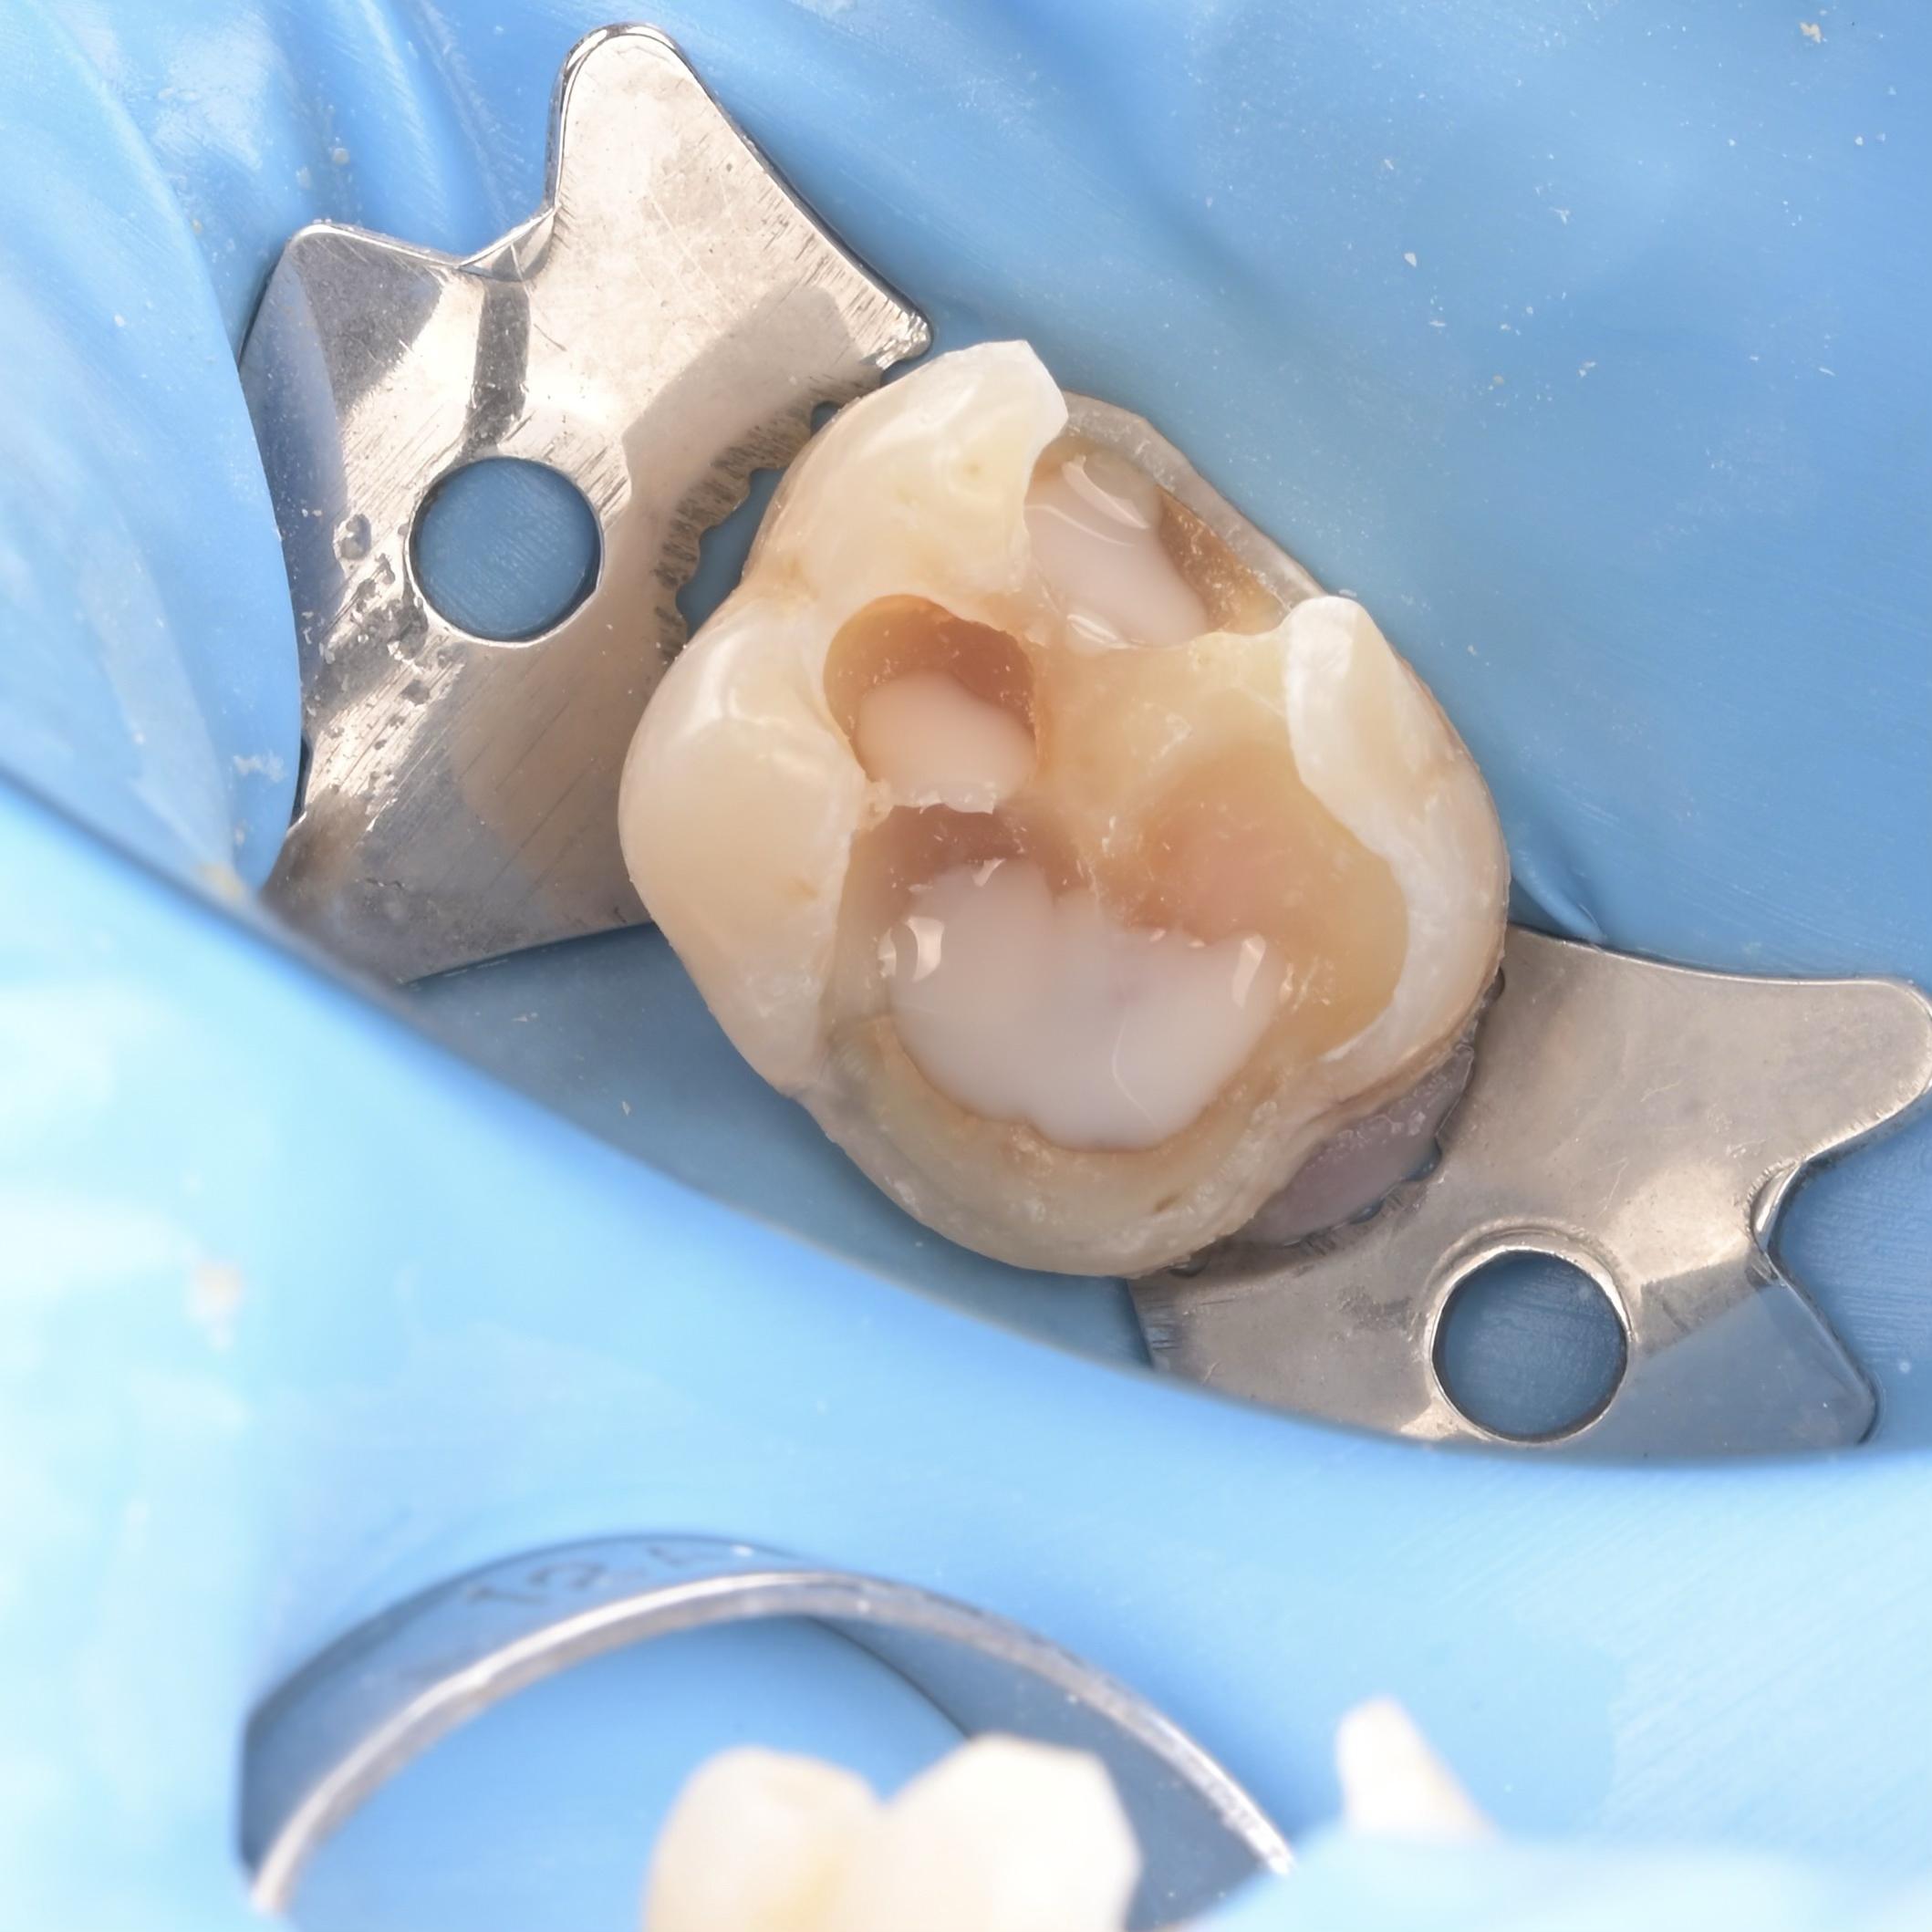

A biomimetikus fogászat egy modern megközelítés, melynek célja, hogy a fogak helyreállítását a fogorvos a természetes fog szerkezetét utánozva végezze el. A módszer kulcsa, hogy a fogat a lehető legkevésbé invazív módon kezelje, maximalizálva a megmaradt egészséges fogszövetet.

Ennek eléréséhez speciális ragasztási technikákat és bio-kompatibilis, üvegszál-erősítésű anyagokat használnak, melyek szorosan kötődnek a foghoz.

A hagyományos koronázással szemben, ahol sok ép foganyagot kell eltávolítani, a biomimetikus eljárásnál csak a sérült részeket távolítják el.

– A betétek (inlay/onlay) olyan nagy kiterjedésű fogtömések, amelyeket a fogtechnikus készít el (a fogon kívül), és speciális ragasztóval rögzít a foghoz, ezzel erősítve meg a megmaradt fogfalat.